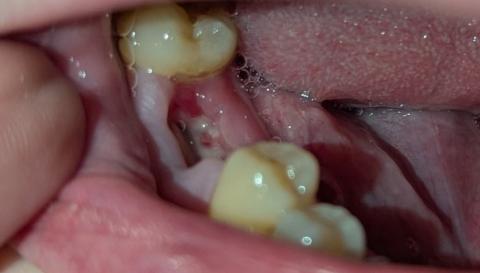

Both Image A and Image B show a dark, well-defined radiolucent area surrounding the root apex of one of the anterior teeth. This appearance is consistent with:

Periapical abscess

Periapical cyst

Chronic apical granuloma

Chronic apical periodontitis